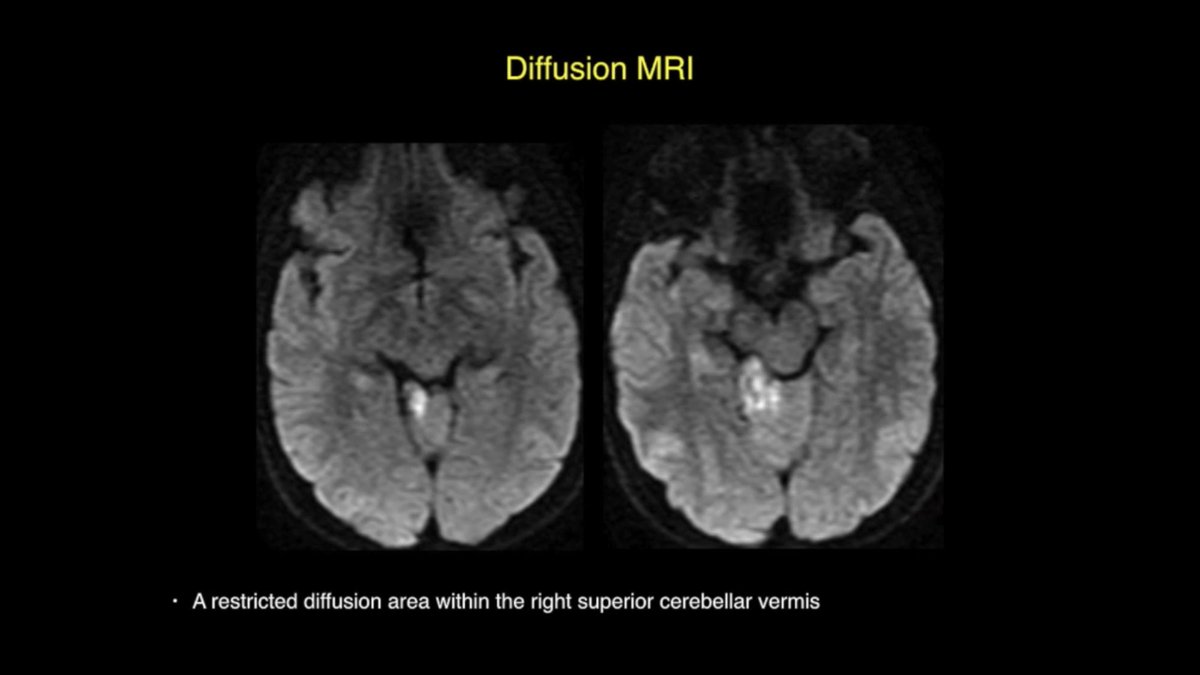

39y M #hemangioblastoma embolized with #onyx, woke up with no sensation in R face, DWI: small restricted diffusion within R superior cerebellar vermis, GTR was uneventful, extruded onyx on #trigeminal nerve & #brainstem was not removed youtu.be/s0DjD26Xkas #nsgy #microsurgery

DrBaskaya's tweet image. 39y M #hemangioblastoma embolized with #onyx, woke up with no sensation in R face, DWI: small restricted diffusion within R superior cerebellar vermis, GTR was uneventful, extruded onyx on #trigeminal nerve & #brainstem was not removed